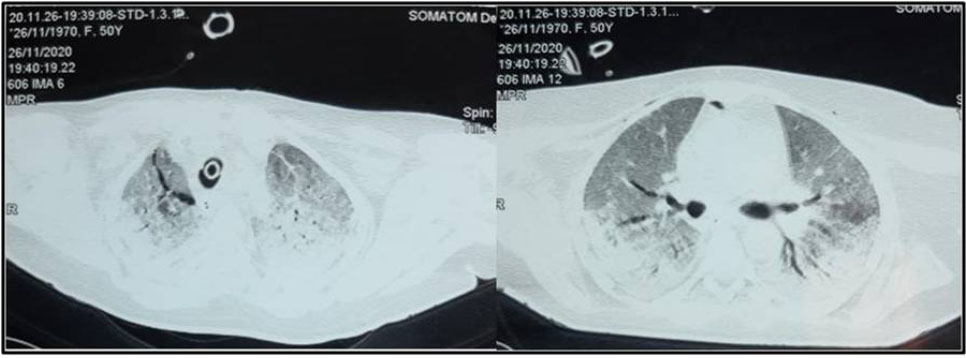

A 61-year-old male patient with past medical history of diabetes was admitted in the pulmonology department for COVID-19 pneumonia. On examination the patient was conscious, febrile at 38.5°C, respiratory rate of 25 breaths/min, hypoxemic with SpO2 on room air of 80% with bilateral crackles on pulmonary auscultation and with stable hemodynamic state. Blood test results showed CRP of 80 mg/L and leukocytes of 8300 cells/mm3. Chest X-ray showed bilateral alveolar and interstitial opacities. A chest CT scan was performed showing bilateral ground-glass opacities with estimated lesions of 30%. He was put under 10 L/min of oxygen with non-rebreather mask with SpO2 of 96%; antibiotics; dexamethasone: 6 mg/day, preventive anticoagulation, famotidine, and vitamins. The patient was transferred three days later to our ICU in front of worsening of his respiratory state with SpO2 of 80% under 15 L/min of oxygen, respiratory rate of 35 breaths/min with struggle signs. He was put under NIV with FiO2: 70–100%, PS: 16–20 cmH2O and PEEP: 6 cmH2O and prone position. A control chest CT scan was performed four days later (after NIV use and slight improvement of the respiratory state) showing: worsening of the bilateral ground-glass opacities with percentage of lesions at 75% associated to a moderate PM (Figure 3). Conservative therapy was adopted with decreasing pressures at NIV (PS: 12–14 cmH2O, PEEP: 4 cmH2O) alternately with high flow nasal cannula oxygenation (HFNC) (flow 50 L/min and FiO2 100%). Unfortunately, five days later, the patient was intubated ventilated under protective ventilation in front of NIV failure with VAC mode Vt: 6 mL/kg of PBW, RR: 26 breaths/min, PEEP: 8 cmH2O and FiO2: 100%. The patient passed away 15 days later in a severe acute respiratory distress syndrome (ARDS) with refractory hypoxemia and shock.

Figure 3: Non-contrast chest CT scan showing worsening of the bilateral ground-glass opacities with percentage of lesions at 75% associated to a moderate pneumomediastinum.